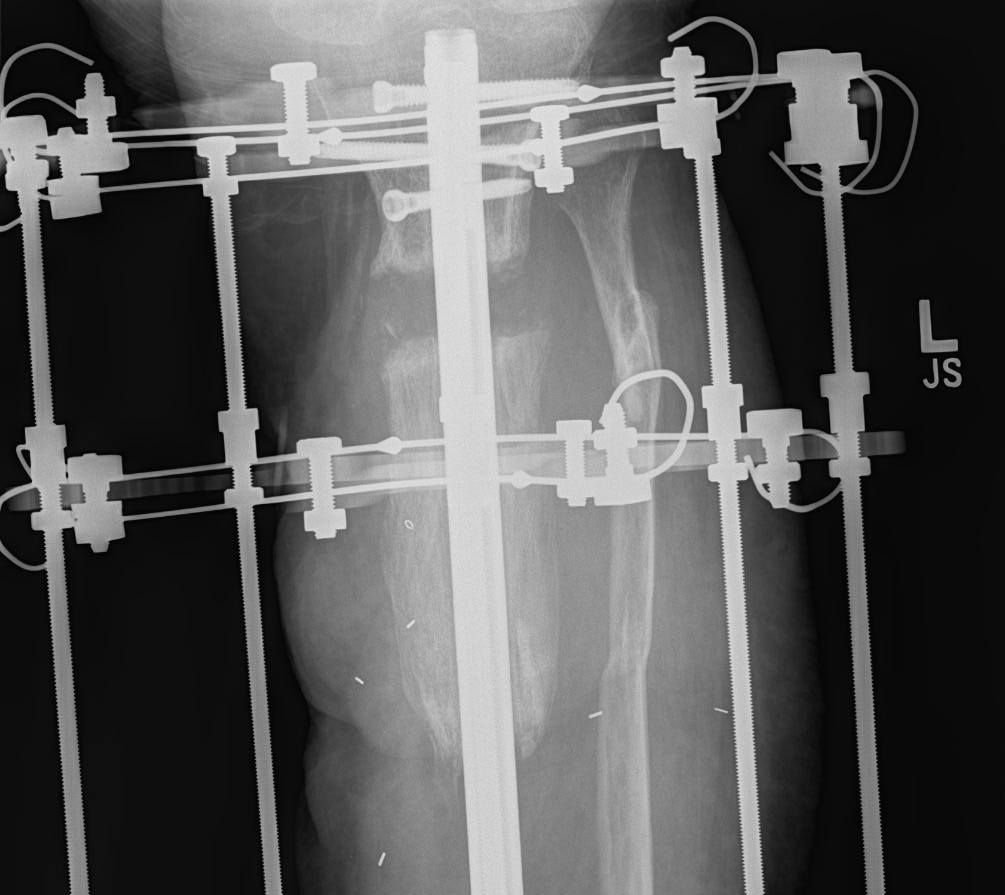

Treatment in ProgressThis x-ray taken during Ilizarov bone transport shows a segment of bone being transported downward over an intramedullary nail into the area of removed bone. |